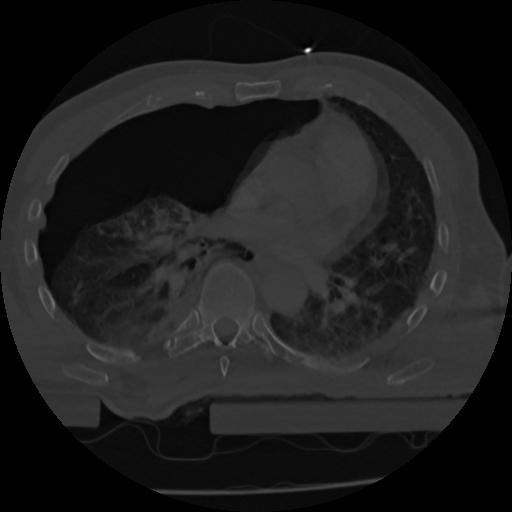

22 ANGIO,CE,Vol,0.5,ANGIO,,